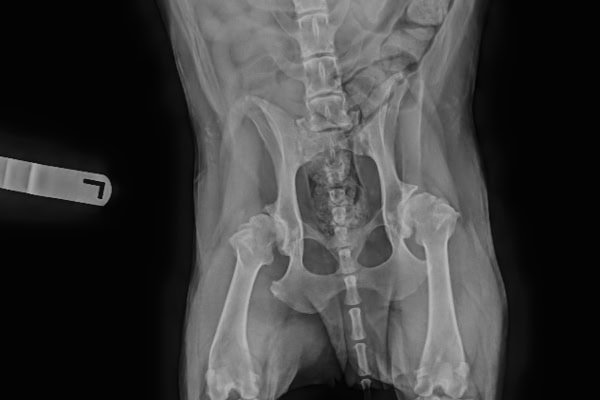

A number of conformational abnormalities make up hip dysplasia in dogs, including:

- A shallow acetabulum

- A flattened femoral head

- A thick femoral neck (the neck of the femur connects the head to the long part of the bone).

These issues can often be seen on X-rays of the hips.